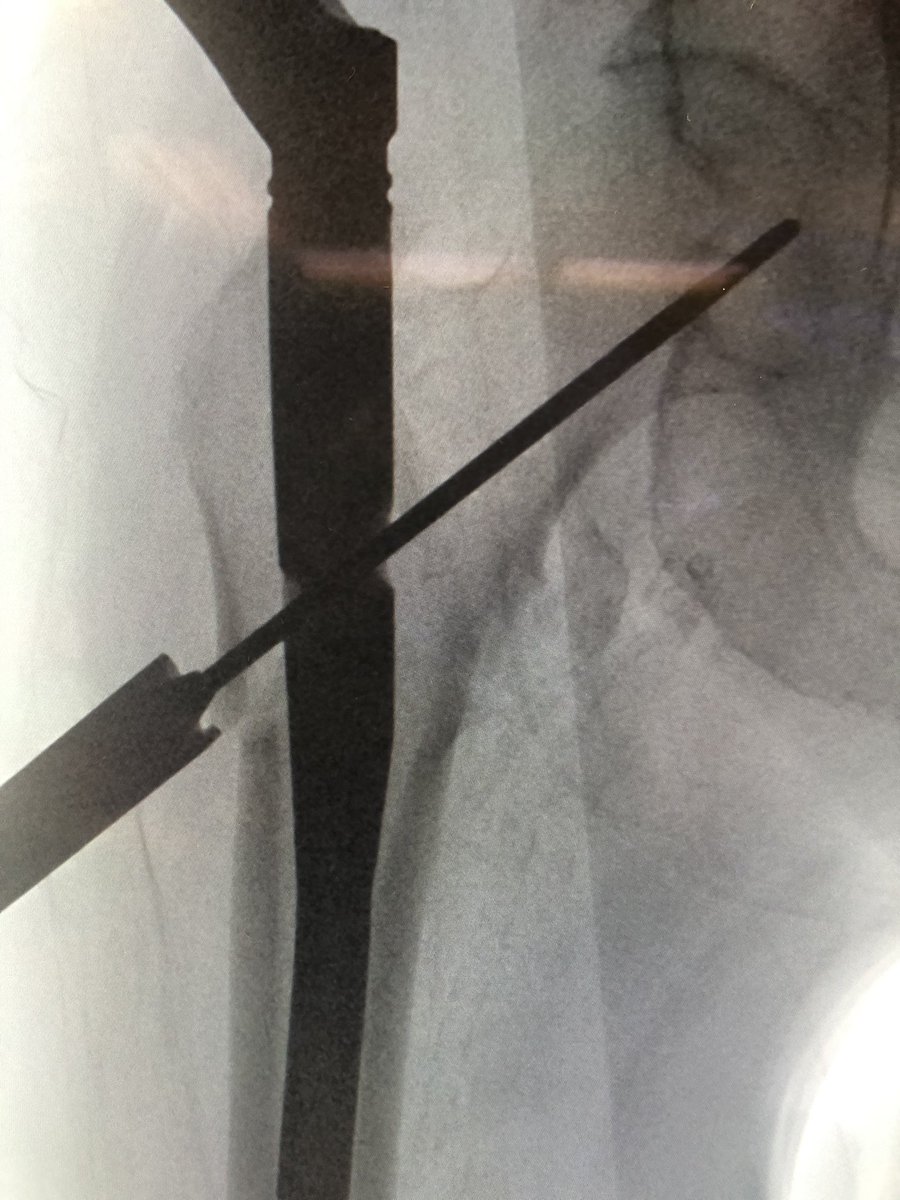

[5/18] Most important: starting point. I draw horizontal line on top of greater troch (green), and hold guidewire up to leg to line up with center of head/neck on perfect lateral & draw line (blue). Stab Incision about 4 finger-breadths proximal / 1 FB anterior to cross of lines.

[6/18] If original start point isn’t good, I leave wire in so new wire doesn’t keep falling into same hole. Also I gently tap to get a foothold instead of using driver so that I can make minute redirections in either plane (yellow). ONLY when I’m happy, I extend stab incision.

[7/18] Once I’m happy with direction, I switch to driver, drive guidewire in metaphysis, then stop and gently tap again. I look for the guidewire to “bounce” off the medial cortex, ensuring it is in bone (not in fracture) and obviating having to go back to the lateral to check.